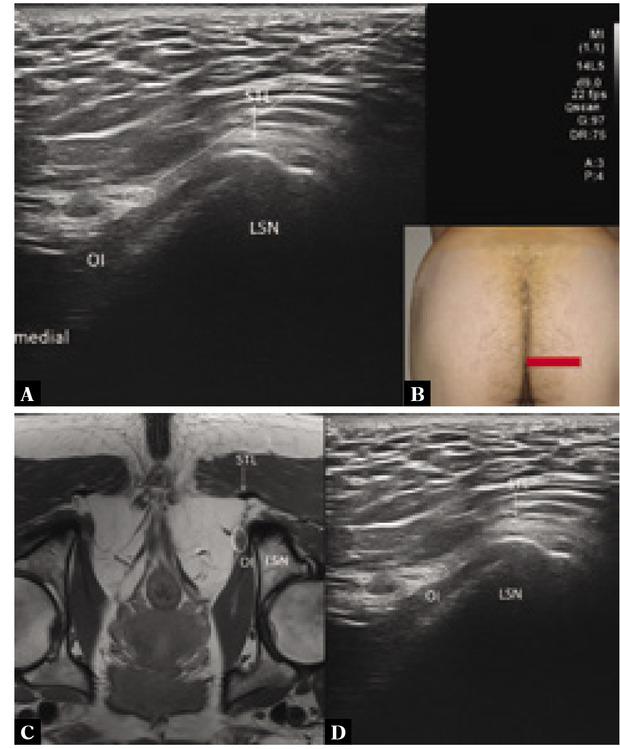

Fig. 4